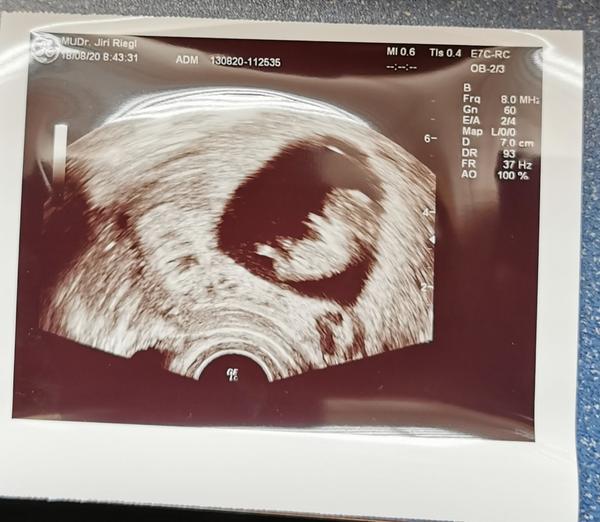

Zdravím holky, chtěla bych vás moc poprosit o radu, vaši podobnou zkušenost. Poslední MS byla 16.6... 17.7 jsem jsi udělala Těhotenský test byli jasně viditelné // 20.7 fotka z ultrazvuku. A teď důvod strachu který mam. Doktor řekl jednu větu která mě znervózněla a od té doby hledám na internetu vše možné a nemožné... Prohlásil že tam není vidět a tudíž budeme ve vašem případě doufat... Další kontrola za měsíc tedy 18.8 a i když se kontrola blíží jsem čím dál víc nervóznější a vyděšená aby to nebylo zamkle těhu.. 😟 moc děkuji za vaše názory

@miskamed tak mám kontrolu za sebou a zatím vše v pořádku 🙂🤗 jsem velký pesimista takže pro mě není vyhráno dokud to malé nebudu držet v náručí, ale jsem klidnější a teď i šťastná 🤗 takže moc držím palce ať to i u tebe dopadne dobře